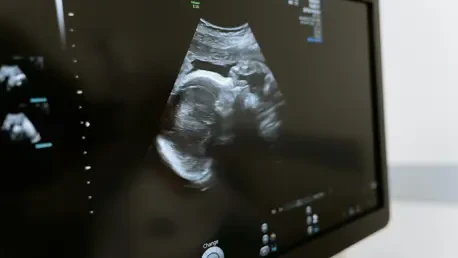

Choosing the right imaging modality is crucial in trauma cases involving pregnant patients, as each tool offers distinct advantages and limitations depending on the clinical context. Ultrasound, particularly through the Focused Assessment with Sonography for Trauma (FAST) protocol, stands as the preferred initial method due to its safety, lack of radiation, and widespread availability in emergency settings. It excels in quickly assessing fetal heart rate and basic uterine integrity in hemodynamically stable patients, providing immediate insights without posing risks to the fetus. However, ultrasound has notable shortcomings, missing up to 80% of placental abruptions—a leading cause of fetal death after maternal shock. Its inability to detect certain maternal or fetal skeletal injuries further limits its scope, often necessitating additional imaging to ensure a comprehensive evaluation of trauma severity.

When ultrasound falls short, other modalities like CT become indispensable, particularly in cases of severe abdominal or pelvic injuries where detailed visualization is critical. Despite involving ionizing radiation, CT is essential for unstable patients, offering rapid and precise detection of life-threatening conditions that might be missed by less sensitive tools. In emergencies, the need for speed often outweighs the minimal radiation risks, and scans may proceed without formal consent to avoid delays. For stable patients, informed discussions about radiation exposure, sometimes involving a medical physicist for fetal dose estimates, can guide decision-making. Additionally, the use of intravenous contrast in CT is considered safe during pregnancy and enhances injury detection, while overly conservative low-dose protocols may lead to repeat scans, inadvertently increasing exposure. This strategic selection of imaging tools ensures that diagnoses are both timely and accurate.